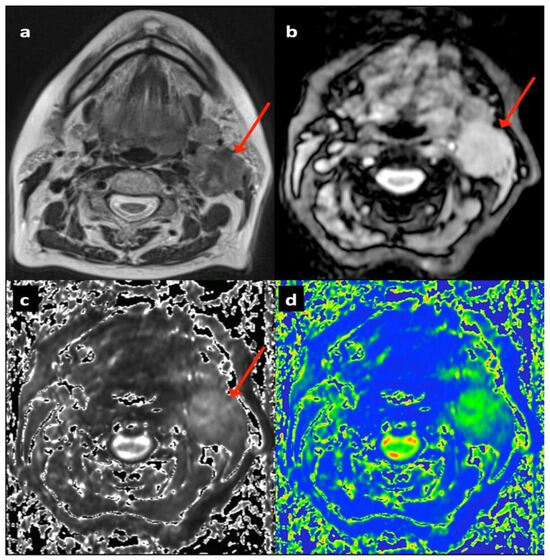

2.2. Multiparametric Magnetic Resonance Imaging

2.3. Image Analysis